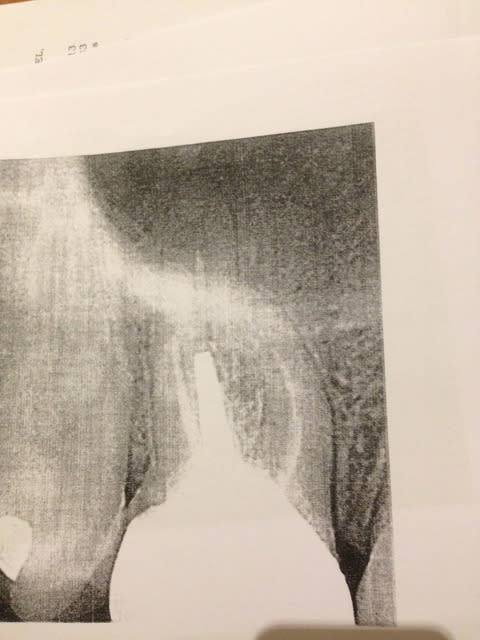

Après il est peut-être convaincu d'avoir raison, mais peut-être faudrait-il qu'il actualise ses connaissances : autre réponses :

" Quant au bien fondé de la décision en elle-même, sur le plan scientifique elle est discutable, doit on attendre la disparition de l'image radiographique pour couronner, ou au contraire couronner au plus vite afin d'assurer l'étanchéité au niveau coronaire le plus rapidement possible afin de limiter le risque de recontamination, le débat est ouvert (personnellement je penche pour la seconde option avec en cas d'échec une petite résection apicale avec obturation à retro, et en cas de nouvel échec un implant avec ou sans rabais) . La NGAP dit qu'on doit attendre mais vu son âge ce n'est pas ce qu'il y a de plus fiable. (on m'a signalé que c'était faux... et après vérification c'est bien faux!)

Cependant en aucun cas ce n'est à l'assurance de trancher! Aucun!"

"Dans tous nos cours on nous dit que la radio est une aide à la prise de décision, en aucun cas elle ne permet à elle seule de poser un diagnostic et un plan de traitement. Ce courrier a tout Faux sur toute la ligne."